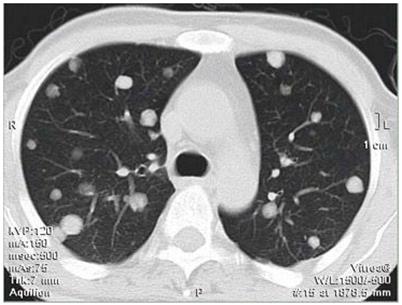

双肺转移癌

全身很多部位的癌症都可以转移到肺部。最常见的有甲状腺癌、乳腺癌、肾癌、绒毛膜癌、骨肉瘤等,肺部转移发生率为60%~90%;其他较容易转移到肺部的恶性肿瘤包括肺癌(从一个肺叶转移到其他肺叶)、肝癌、胃癌、结直肠癌、前列腺癌等,肺部转移发生率为35%~55%。